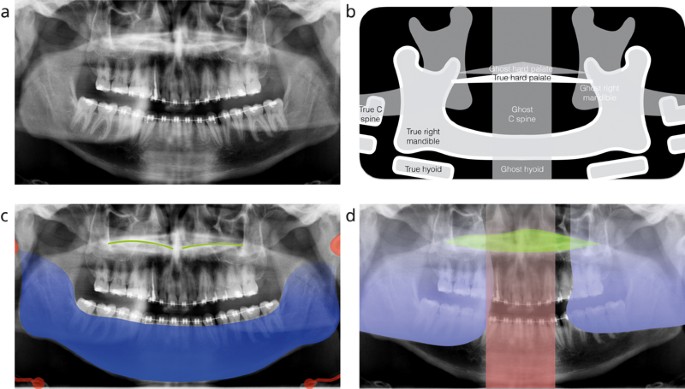

Panoramic Radiography Normal Anatomy And Ghost Images Unit

Thus images of multiple planes are taken to make up the composite panoramic image where the maxilla and mandible are in the focal trough and the structures that are superficial and deep to the trough are blurred. The panoramic image indicates a flattened condyle and significant wear of the glenoid fossa of the temporal bone due to constant force from bruxism and clenching. Hitting enter or pagedown will also work.

Although it is obvious that a panoramic radiograph depicts the teeth and jaws in a single convenient view it may be less clear how the other structures of the head and neck become captured on the image. It was also noted that the patient has very pronounced styloid processes bilaterally. The maxillary sinus appears on the panoramic image as a radiopaque structure.